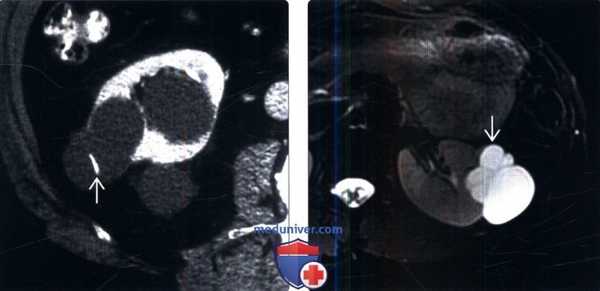

(Слева) КТ с контрастированием, аксиальная проекция: множественные кистозные образования водной плотности, включая одно с тонкой кальцинированной перегородкой (класс 2 по Босняку).

(Справа) МРТ, Т2-ВИ, режим подавления сигнала от жировой ткани, аксиальная проекция: дольчатая киста левой почки с множественными внутренними тонкими перегородками. Несмотря на небольшую толщину, перегородки хорошо контрастированы на Т1-ВИ с контрастированием Гд (изображения отсутствуют). Это образование — киста класса 2F по Босняку, что требует наблюдения с КТ- или МРТ-визуализацией.